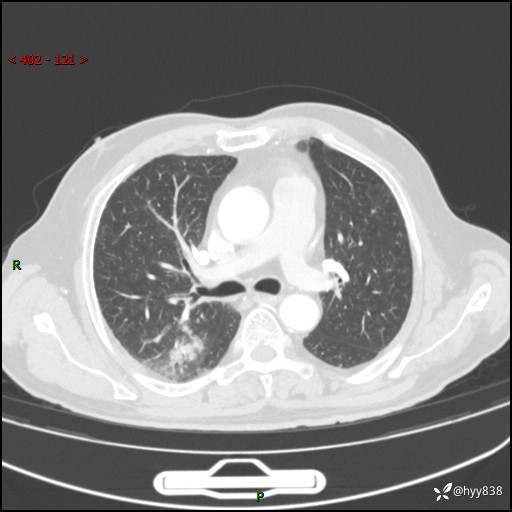

胸部CT复查(2024.7)